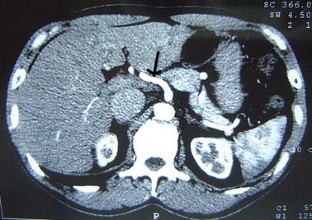

A variation in liver vascularization was discovered in a 50-year-old man. A single common hepatic artery was found to be responsible for vascularization of the entire liver. This artery was unusual in that it formed the first branch of the superior mesenteric artery, crossing the portal trunk shortly after its origin, and passed in front of the portal vein to reach the hilum of the liver, where it divided into a right and a left branch. This artery was a true common hepatic artery because a gastroduodenal artery emerged from it 2 cm after its origin. A common hepatic artery originating from the mesenteric artery and passing in front of the portal vein has never been described before. The patient had a second anatomical variation: the left gastric artery and the splenic artery arose directly from the aorta, without celiac trunk separation. This observation confirms the importance of carrying out a precise vascular assessment before all types of hepatic or pancreatic surgery, to identify possible variations in the number or trajectory of hepatic arteries.

Fig. 1